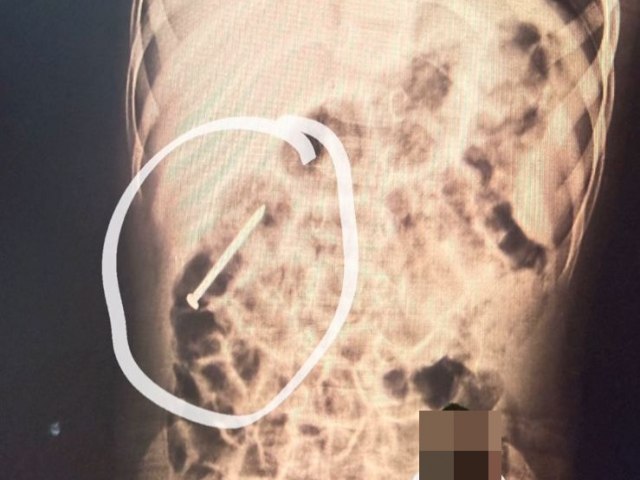

Um menino de 2 anos, morador do município de Ipixuna, está internado no Hospital do Juruá após engolir um prego há cerca de seis dias. O caso segue sendo acompanhado pela equipe médica da unidade.

De acordo com profissionais de saúde, o objeto metálico está avançando pelo aparelho digestivo da criança de forma natural. Por precaução, o menino permanece hospitalizado para monitoramento contínuo, enquanto se aguarda a eliminação do material sem a necessidade de intervenção médica.

O estado de saúde da criança é considerado estável, apresentando boas condições clínicas até o momento. A equipe médica segue realizando exames e acompanhamento para garantir que não haja complicações durante o processo.